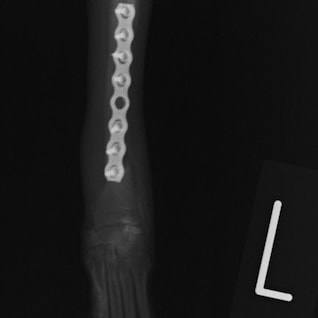

トイプードル 右遠位橈尺骨短斜骨折のALPSによる内固定